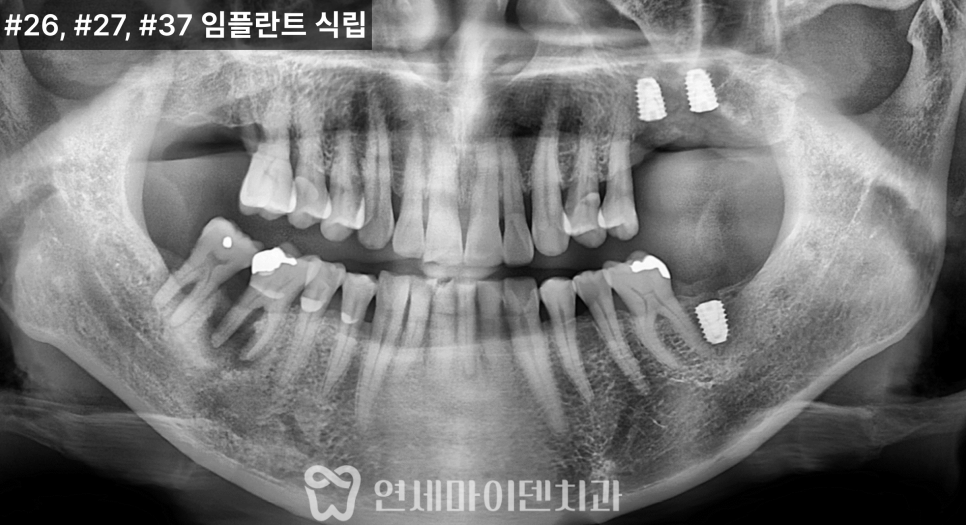

치료 전 방사선 사진을 보면

치아가 쓰러진 문제도 있었지만

무엇보다 뼈의 폭과 높이가

많이 줄어든 상태

였습니다.

잇몸도 전반적으로 약했고,

1차 수술: 발치, 염증 정리, 식립과 이식 동시 진행

첫 단계에서는

아래 1개, 위 2개

3개의 임플란트를 계획했습니다.

위쪽은 상악동이 내려와 있어

상악동 거상술과 뼈이식을 함께 시행한 뒤

그 공간에 임플란트를 식립했습니다.

아래쪽은 뼈 상태가 비교적 유지되어 있었지만

안정적인 고정을 위해

필요한 부위에 뼈이식을 병행했습니다.

즉, 발치가 필요한 부위는 발치를 하고

염증을 정리한 뒤

식립과 뼈이식

하루에 함께 진행한 케이스였습니다.